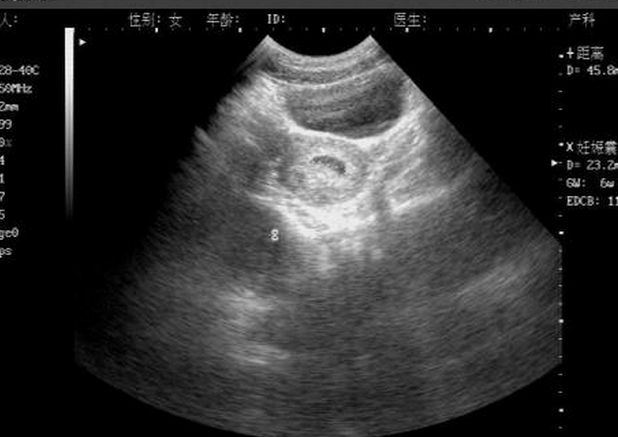

正常情况下,孕30-40天胚胎孕囊形成;孕40-50天,胎芽形成;孕50-60天

一般情况下,在怀孕40天左右,通过b超检查可看到孕囊大小,孕囊位置